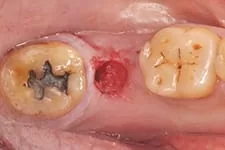

3. 即拔即種

打破傳統即拔即種(又叫立即植牙),拔牙後立刻植牙。患者可在拔牙後立即植入人工植體,並立刻裝戴假牙。讓你治療當天就能擁有美觀的門面。

我們在植牙領域的突破,克服患者對手術的恐懼,也同時幫助患者告別了缺牙的痛苦,讓患者重新擁有一口完美的牙齒。

↑ 治療後:微創立即植牙恢復美麗外觀